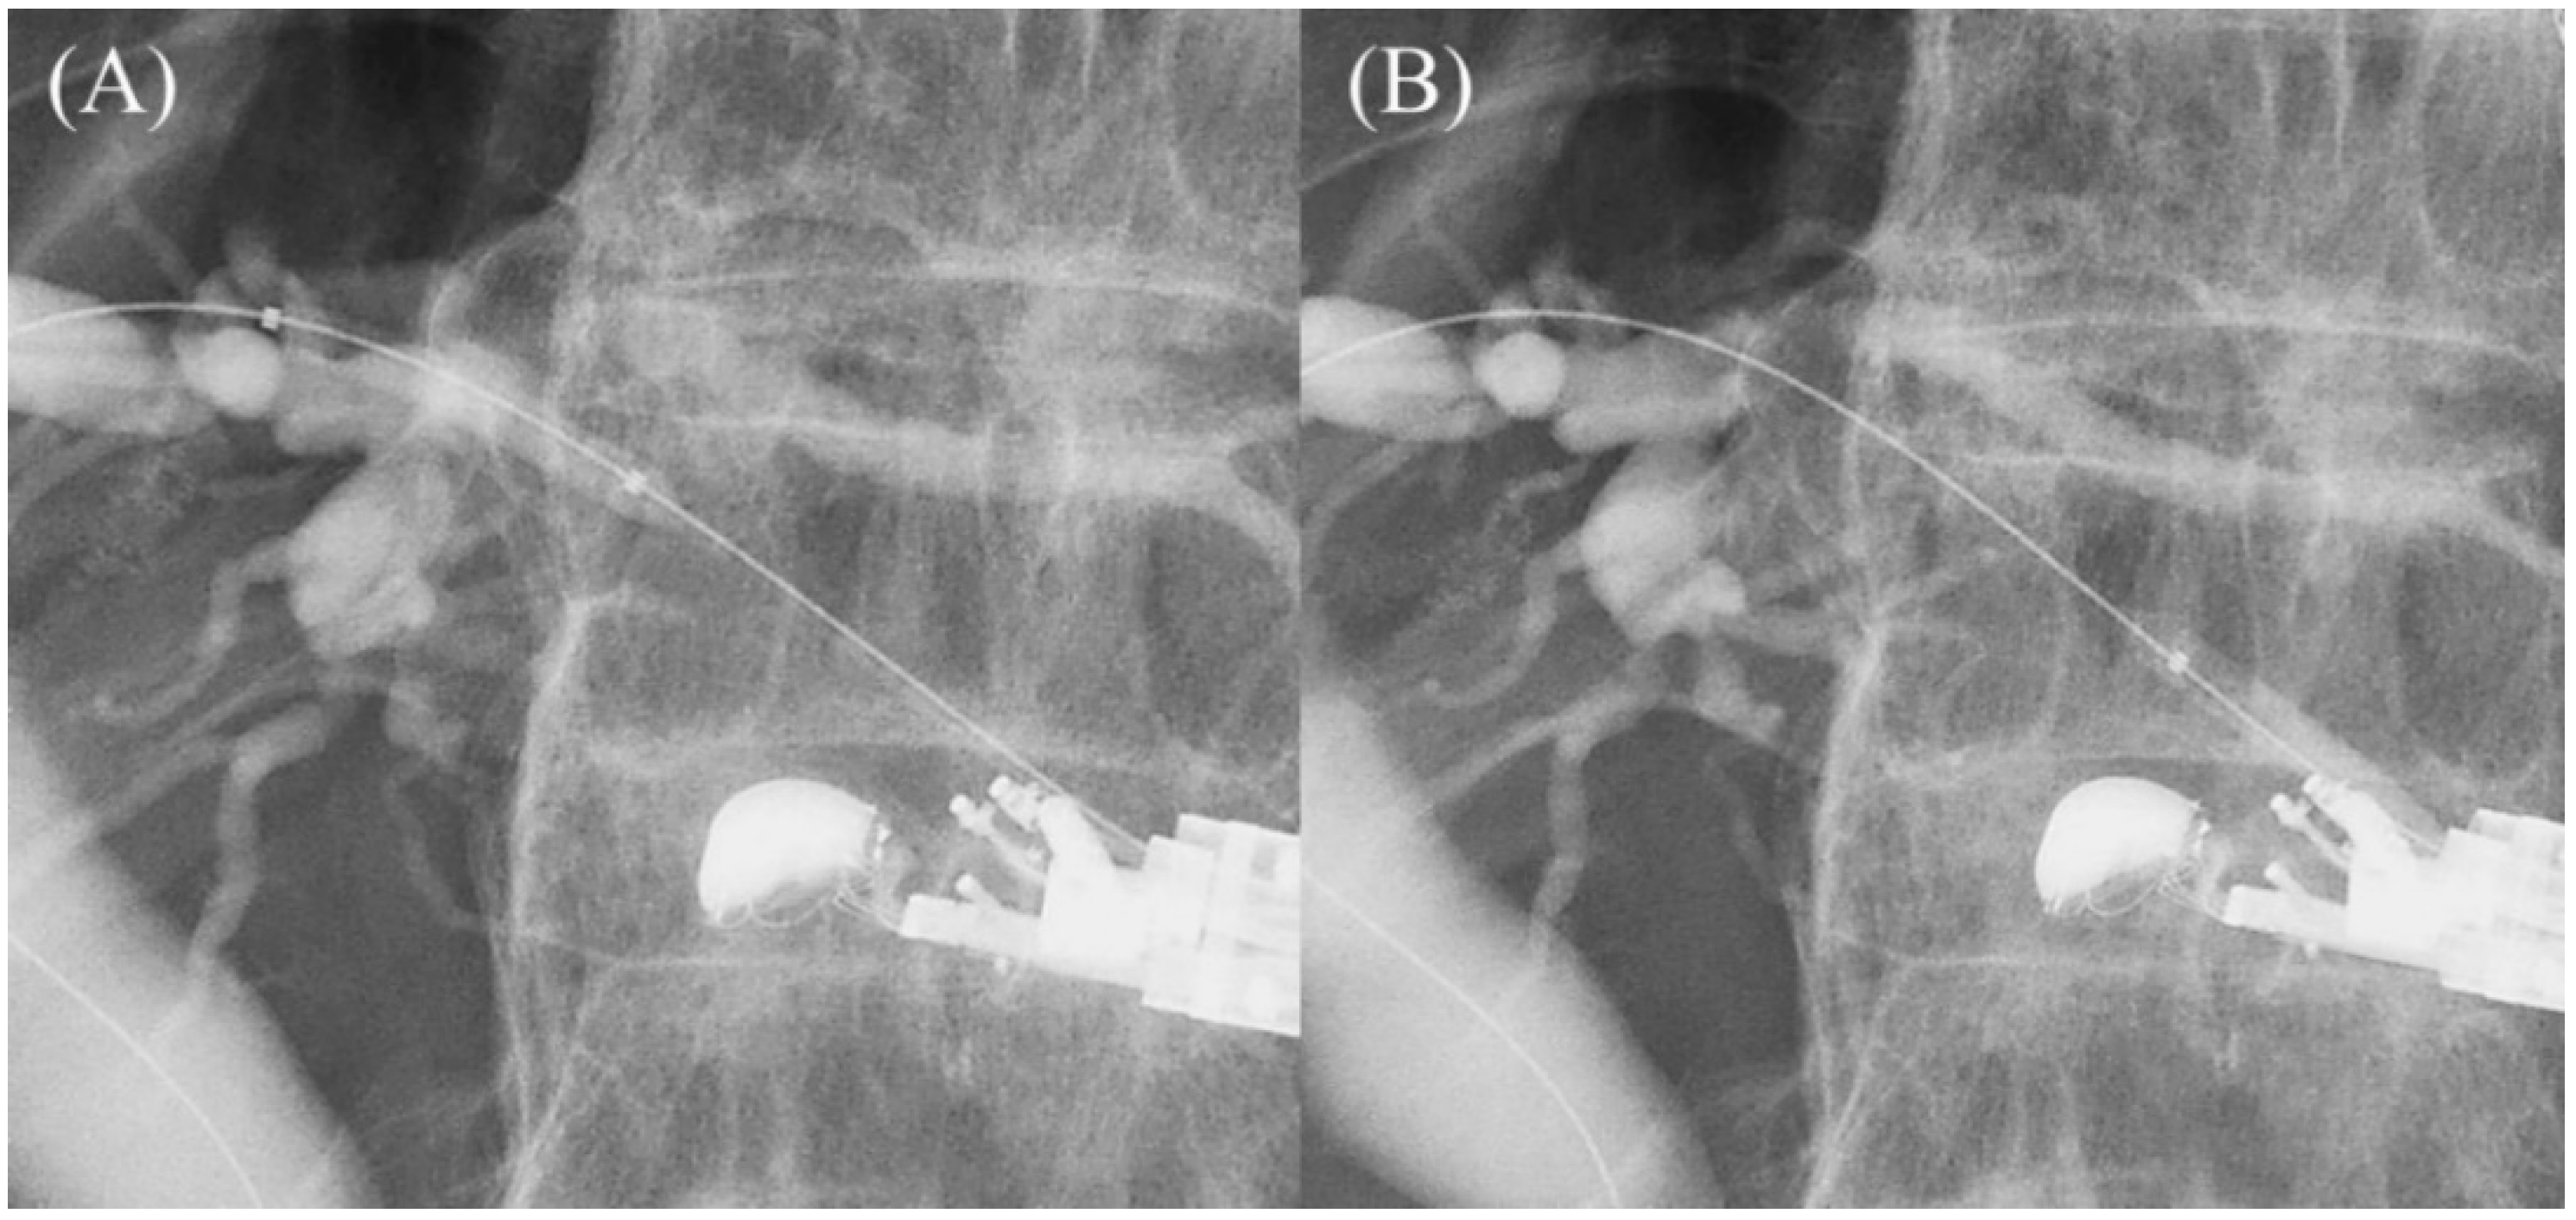

Figure 2.

Too shallow echoendoscope position in B3 puncture. In a shallow scope position, the angle formed by a needle and the bile duct on the hilar side is often acute, and a guidewire can easily go to the peripheral side ((A); ultrasound image, (B); fluoroscopic image).

Figure 3.

Optimal echoendoscope position in B3 puncture. Pushing a scope while turning the large wheel upward rotates the EUS image clockwise and makes the angle between a needle and the bile duct on the hilar side obtuse, making a guidewire manipulation toward the hilar region easy (A). Fluoroscopic image (B).